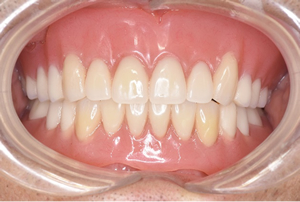

81歳、上下精密義歯

院長(46歳、欠損なし)

*ほぼ同じ値ですが、 上下精密義歯装着者の方が、私より高い数値が出ています!!